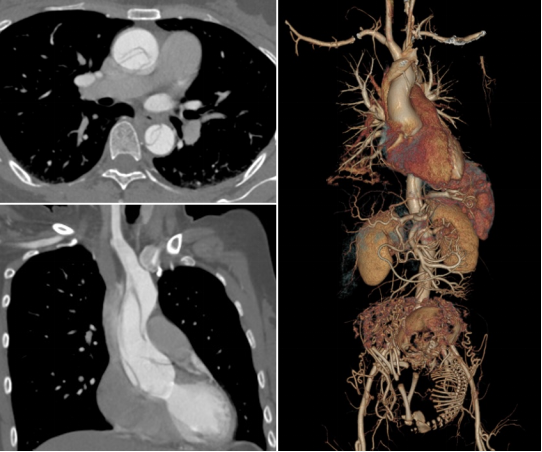

术前CTA提示孕妇罹患Stanford A型主动脉夹层

孕期A型主动脉夹层

急性主动脉夹层是一种极其凶险的心血管危急重症,患者主动脉内膜撕裂,血液流入内膜与中膜之间,导致血管壁分层,使得部分主动脉管壁仅剩一层薄薄的外膜,犹如一颗“定时炸弹”,极易发生破裂,造成患者大出血死亡。A型主动脉夹层发病24小时内死亡率高达33%,每过1小时死亡率递增1%。孕期合并主动脉夹层十分罕见,发病率约为百万分之五,孕妇和胎儿的死亡率分别可高达30%和50%。